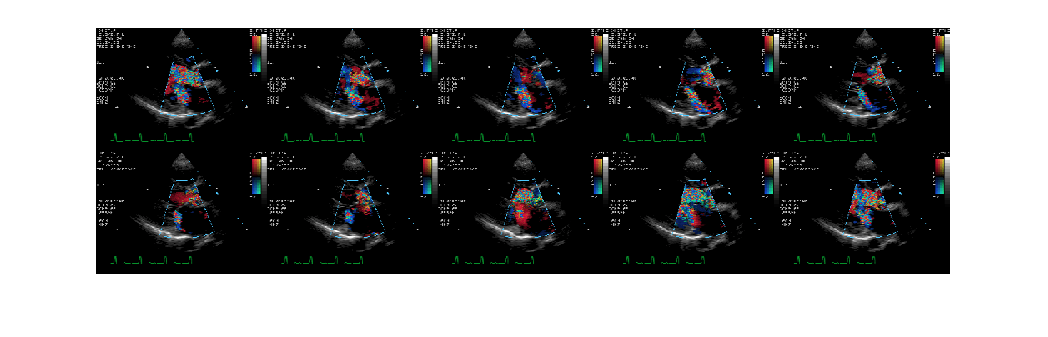

Считайте индексированное изображение из файла DICOM и отобразите его с помощью montage.

[X, map] = dicomread('US-PAL-8-10x-echo.dcm');

montage(X, map, 'Size', [2 5]);

Figure contains an axes. The axes contains an object of type image.